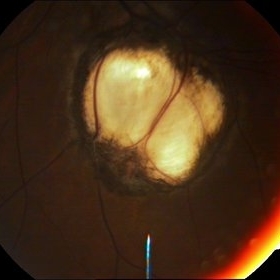

Choroidal Coloboma

15-year-male patient presented with for routine check up was found to have colobomas not involving disc and macula.

Condition/keywords: choroidal coloboma